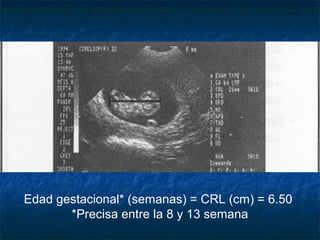

Embrión de 7 SemanasEmbrión de 7 Semanas

Edad gestacional* (semanas) = CRL (cm) = 6.50

*Precisa entre la 8 y 13 semana